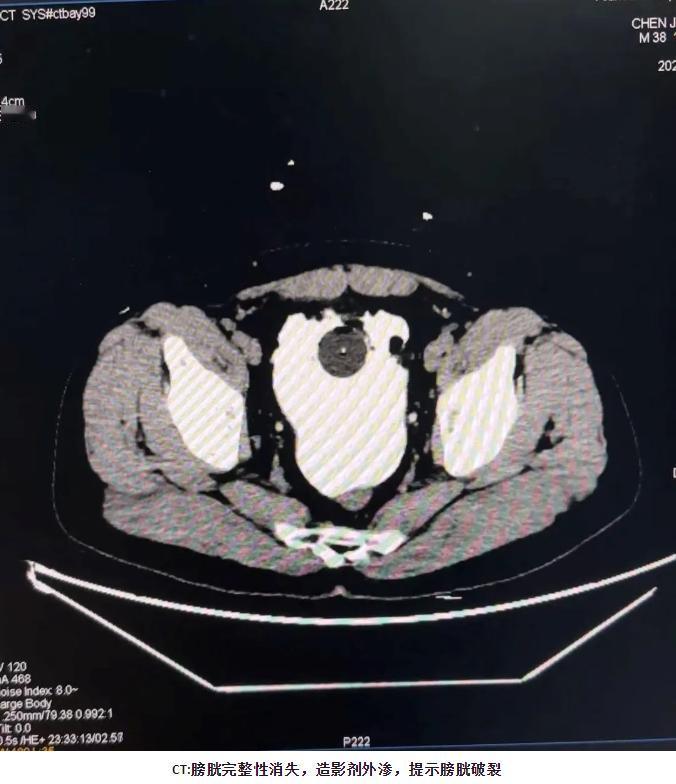

看完陕西这大哥的遭遇,我刚端起的水杯都放下先去了趟厕所! 西安的王先生跟朋友喝啤酒,8瓶下肚明明有尿意却硬扛,想着回家再解决。结果半夜被肚子剧痛疼醒,冲到马桶前憋得直冒汗,却只挤出几滴尿,吓得赶紧往医院跑。 医生一查直接说膀胱裂了个6cm的洞!原来他喝到深度醉酒,大脑被酒精“麻住”,没接收到膀胱满了的信号,膀胱撑到极限,一个翻身就裂开了,尿液还流进腹腔,手术补好后还可能留后遗症。 别觉得憋尿是小毛病,尤其喝了酒,身体反应变迟钝,风险比平时翻好几倍。你们平时聚会喝酒,会因为怕扫兴致硬憋不上厕所吗?